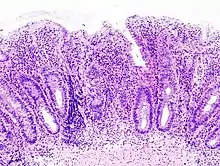

Histologic

Biopsies of the mucosa are taken during endoscopy to confirm the diagnosis of UC and differentiate it from Crohn's disease, which is managed differently clinically. Histologic findings in ulcerative colitis includes: distortion of crypt architecture, crypt abscesses, and inflammatory cells in the mucosa (lymphocytes, plasma cells, and granulocytes).[28] Unlike the transmural inflammation seen in Crohn's disease, the inflammation of ulcerative colitis is limited to the mucosa.[28]